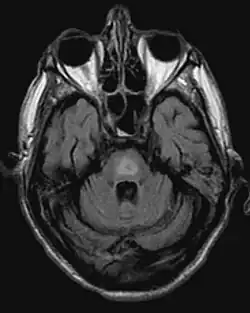

- Magnetresonanztomographie (Veränderungen oft erst nach einigen Wochen!)